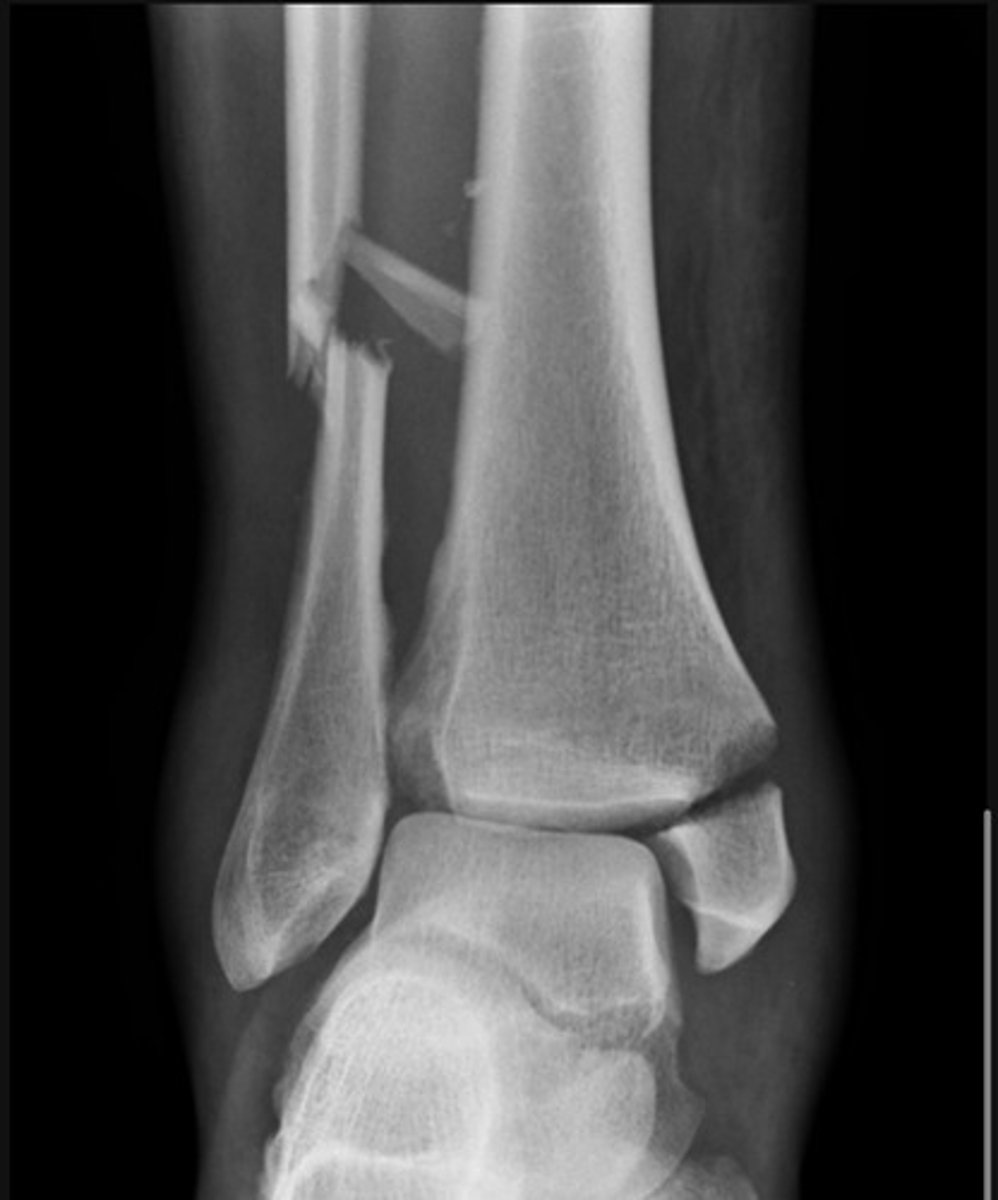

What is a Maisonneuve fracture?

A proximal fibula fracture associated with an ankle injury

Weber C

There is a transverse medial malleolus fracture

The distal tibiofibular joint is also widened